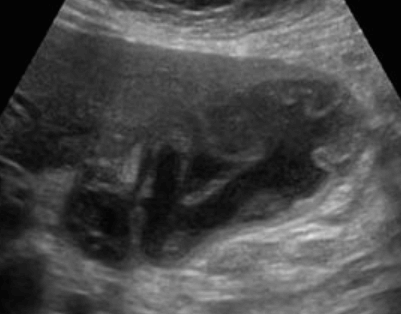

US finding

- 담낭이 비대해지고 담낭벽이 비후 된다

- 담낭 내 격막이 있다